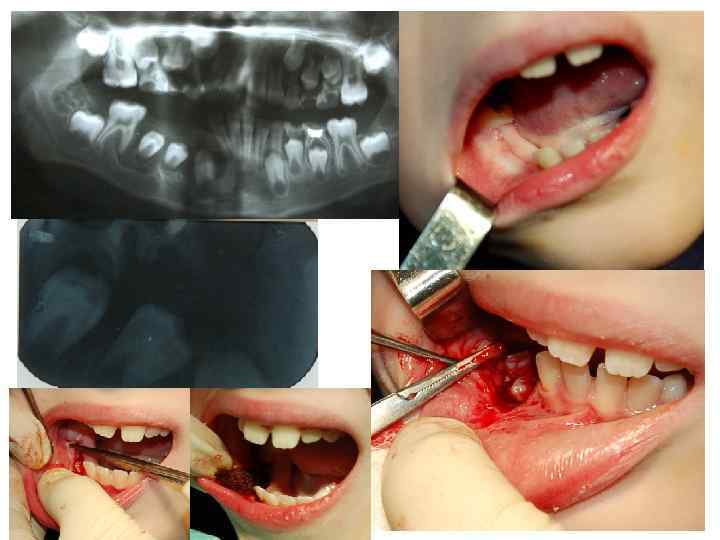

• Биопсия — метод получения ткани живого организма для • • морфологического исследования с диагностической целью. Существует несколько способов диагностических биопсий, используемых в стоматологии: —инцизионная биопсия — иссекается только часть новообразования (при этом размеры иссекаемого фрагмента должны быть не меньше 1, 0 x 1, 0 см, иначе возникают трудности в трактовке морфологической картины для патологоанатома); — эксцизионная биопсия — иссекается вся опухоль. Этот вид биопсии применяется при небольших новообразованиях; — трепанобиопсия, с высверливанием части костных и хрящевых объектов; — пункционная биопсия — выполняется специальными иглами (например, игла Пятницкого), позволяющими получить столбик ткани. Применяется при глубоко расположенных новообразованиях. Этот вид биопсии можно использовать для морфологического исследования увеличенных лимфатических узлов. • Иссеченный участок опухоли должен быть осмотрен хирургом и подробно описан в истории болезни (размеры, консистенция, цвет, характер поверхности, вид на разрезе). После этого материал должен быть помещен в 10% раствор формалина и немедленно промаркирован с указанием фамилии, имени и отчества больного, фамилии хирурга, выполнявшего биопсию.

Дополнительные методы исследования и окончательная диагностика Инвазивные 1. Метод инцизионной биопсии. По материалу пунктата трудно отличить гиперпластические процессы от опухолевых поражений. В этих случаях предпочтительнее инцизионная биопсия опухоли и лимфатического узла. Биопсия опухоли у ребенка должна проводиться только в условиях детского специализированного стационара.